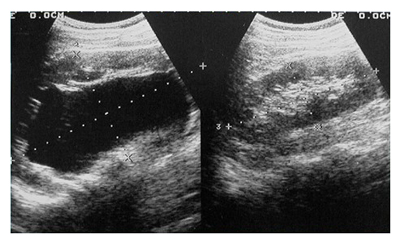

УЗИ почек ребенку

Как было отмечено ранее, ультразвуковое исследование почек является совершенно безопасным методом диагностики, что позволяет проводить его как взрослым, так и детям. При проведении процедуры важно учитывать возрастные особенности анатомии органа.